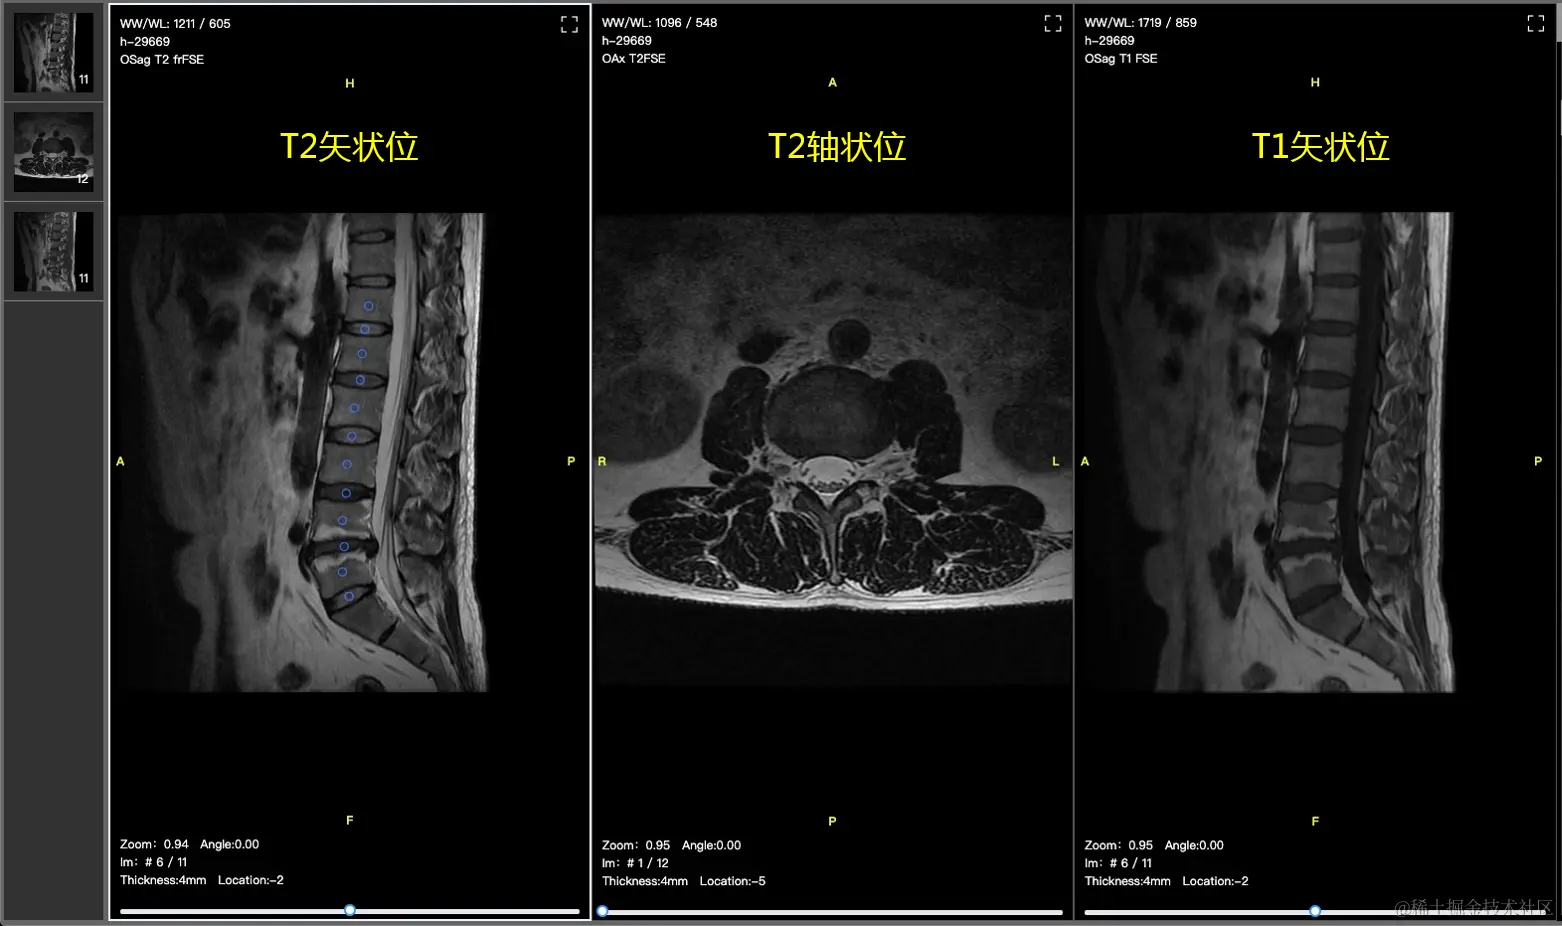

Spinal Disease Dataset: 脊柱疾病核磁影像数据集。脊柱退化性疾病,如腰椎间盘突出等症状正呈现出年轻化的趋势,困扰着老年人群体和办公族,正确的预防和干预能够有效防止疾病的恶化。核磁(MRI)作为非侵入式检查手段,适合对普通人群的常规检查,是预防脊柱退化性疾病的可靠检查手段。天池联合湘雅医院、万里云等单位开放了业界首个脊柱MRI数据集,目标是促进研究者们关注人工智能算法在脊柱退化性疾病的研究。